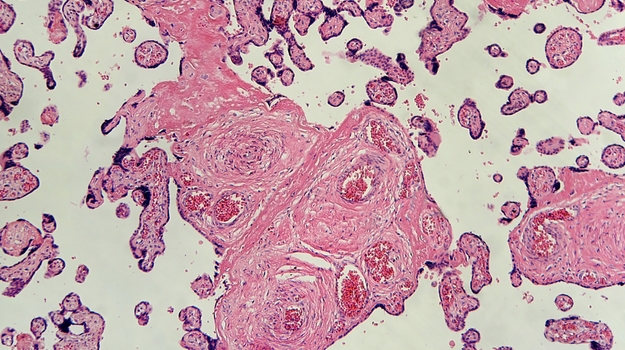

PLX细胞源自年轻健康的供体的胎盘,这些供体具有C形切片(在知情同意后)。胎盘素提供了一种道德的细胞来源,它们很容易获得,而且供应量几乎是无限的。“一个胎盘可以产生20,000剂。”